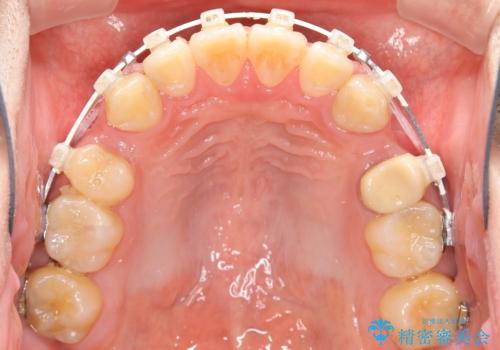

出っ歯、ガタつきの改善 ワイヤー矯正治療

- 矯正装置

- 審美装置

- 上顎前歯の突出感と下顎前歯のガタつきが主訴で来院されました。

出っ歯とガタつきの改善を行うには抜歯が必要と診断し、上下左右第一小臼歯を抜歯する計画を立てました。

抜歯する事で歯の移動量が大きいことからワイヤー表側矯正装置で治療を行うことになりました。